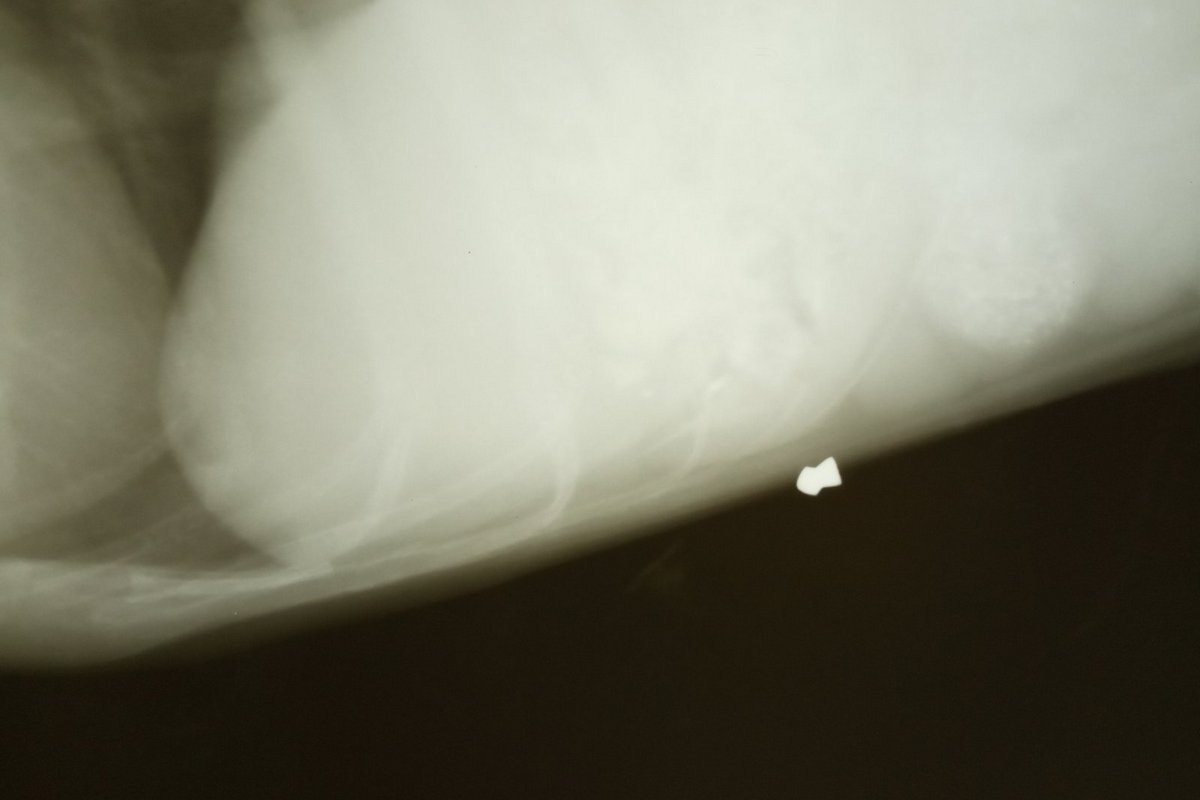

Вместе с тем, одна из собак помощи так и не дождалась. Вторая - в тяжелом состоянии находится под присмотром врачей. Зовут песика Лайм. У него увеличено сердце, есть сердечный кашель, нарушена флора, еда не переваривается и не усваивается (последствия тотального голода), желудок забит землей, которую собака ела, чтобы жить. Кроме этого, у собаки под грудиной пуля от пневматической винтовки. Животному нужно срочно провести обследование, УЗИ и допплерометрию. Все это - не трехзначная и, возможно, даже не четырехзначная сумма. Плюс ко всему, у волонтеров долг на сегодня составляет 4700 гривен.